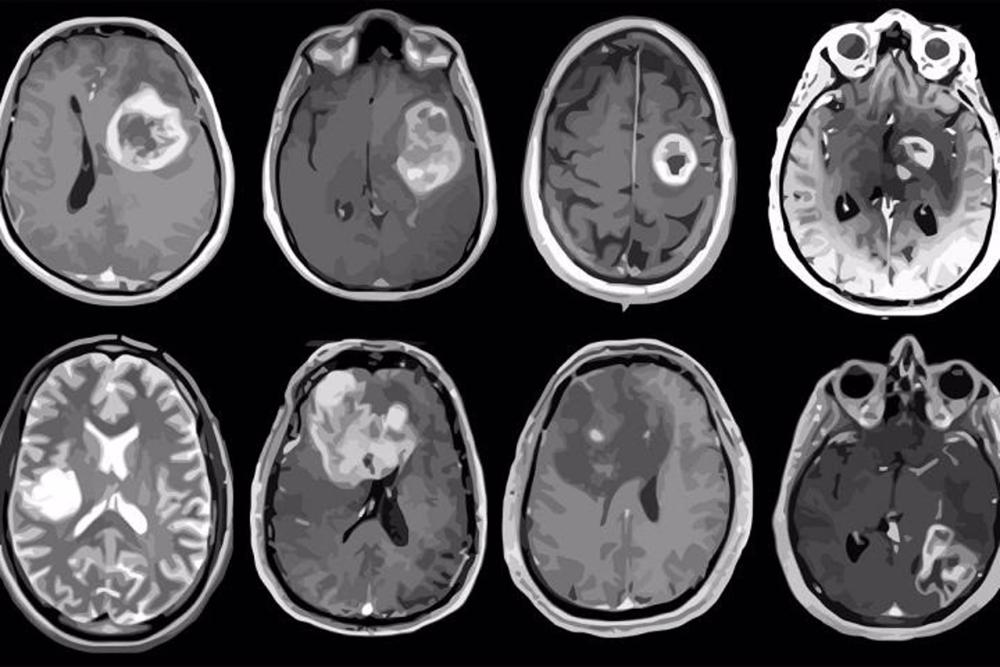

Un equipo de neurocirujanos e ingenieros de varias universidades estadounidenses ha desarrollado un sistema de diagnóstico basado en inteligencia artificial (IA) que utiliza imágenes rápidas para analizar muestras tumorales tomadas durante una operación y detectar mutaciones genéticas con mayor rapidez, en menos de 90 segundos.

En un estudio de más de 150 pacientes con glioma difuso, el tumor cerebral primario más común y mortal, el sistema recién desarrollado identificó mutaciones utilizadas por la Organización Mundial de la Salud (OMS) para definir subgrupos moleculares de la afección con una precisión media superior al 90 por ciento.

Antes de este sistema, denominado ’DeepGlioma’, los cirujanos no tenían un método para diferenciar los gliomas difusos durante la cirugía. El sistema, una idea que comenzó en 2019, combina redes neuronales profundas con un método de imagen óptica para obtener imágenes del tejido tumoral cerebral en tiempo real.